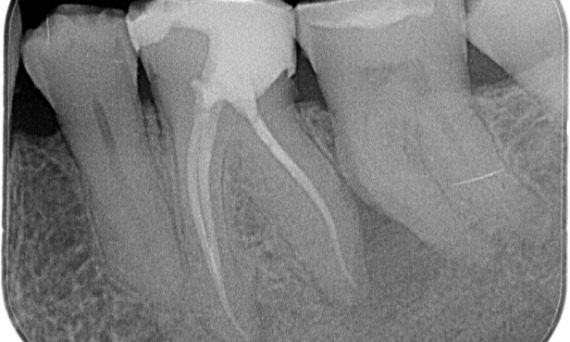

Before: Upon examination, there was a caries lesion related to the lower right first molar. Radiographic examination revealed proximity of the lesion to the pulp horn and combining it with the chief complaint, a final diagnosis of chronic irreversible pulpitis was concluded.

After: Access cavity was done as conservative as possible. TruNatomy was the system of choice due to the young patient’s age. We needed to preserve dentine as much as possible to increase the tooth ability to overcome occlusal load and increase the longevity of the final restoration.